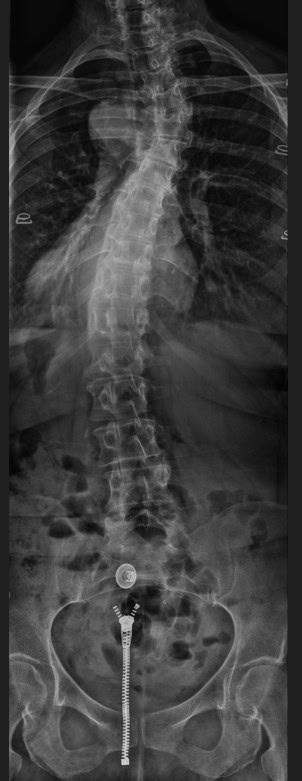

Post Scan